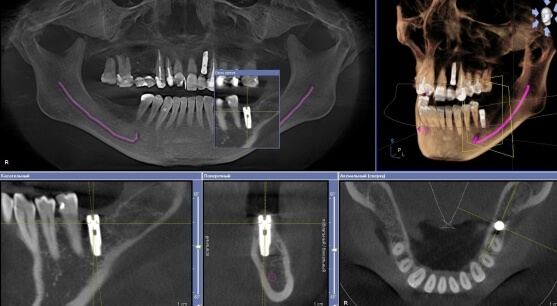

Результаты томографического обследования представляют собой 3D – модель зубочелюстной системы пациента, которая отображает данные сразу в трех плоскостях:

- Сагиттальной

- Фронтальной

- Аксиальной

3D – исследование позволяет получить четкую информацию о строении и структуре костной ткани, об индивидуальных особенностях расположения зубов и их корней, о наличии воспалительных процессов и много другой информации, необходимой для точного диагностирования. Качественный снимок зуба дает возможность визуализировать информацию не только общего характера, но и буквально по каждому зубу и участку челюсти. Так же специалисты клиники рекомендуют делать и прицельный снимок зуба, для более детальной диагностики по конкретной проблемной области. Обычно его можно сделать после консультации, либо сразу, когда Вам назначили панорамный снимок зубов.

3D снимок зубов необходим для более точной операции при имплантологии и опртопедии, а так же при диагностике ЛОР заболеваний. Трехмерная 3D компьютерная томограмма отличается от классического плоского (2D) рентгеновского снимка примерно также, как плоская фотография от окружающего объемного реального мира.

Получив 3D обследование, Ваш врач сможет рассматривать объемные 3D снимки ваших зубов, исследовать со всех сторон интересующие его области, что недоступно на обычном плоском рентгеновском снимке. Теперь он сможет поставить точный диагноз, правильно спланировать лечение и избежать возможных осложнений.